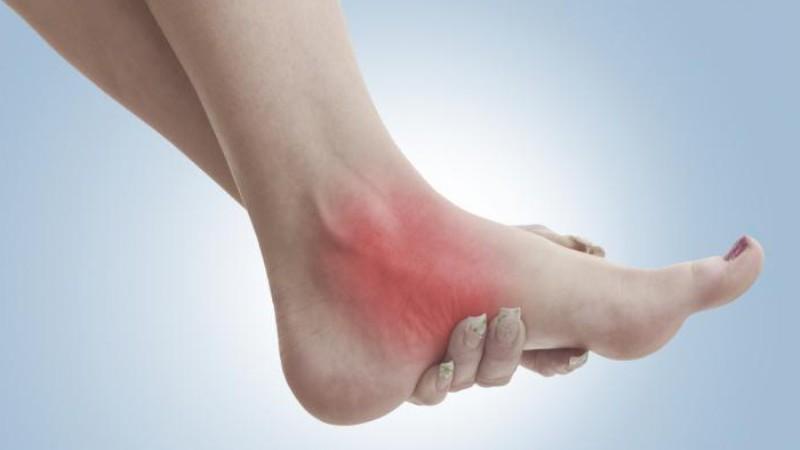

Некроз пятки, точнее, таранной кости, на ранних стадиях практически не проявляется и не вызывает дискомфорта у человека.

Тем не менее, по мере прогрессирования заболевания можно заметить следующие характерные симптомы:

- болевые ощущения в области лодыжки;

- возникновение отечности;

- хромота;

- ограничение подвижности.

Со временем симптомы становятся более выраженными из-за распространения патологического процесса и ухудшения функциональности.

Человеку становится сложно передвигаться самостоятельно. Боль становится постоянной и интенсивной. Все это делает невозможным ведение полноценной жизни.